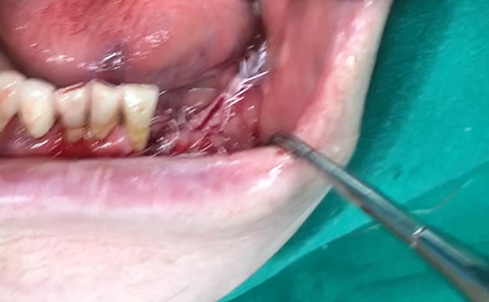

Simultaneous bone graft and implant placement